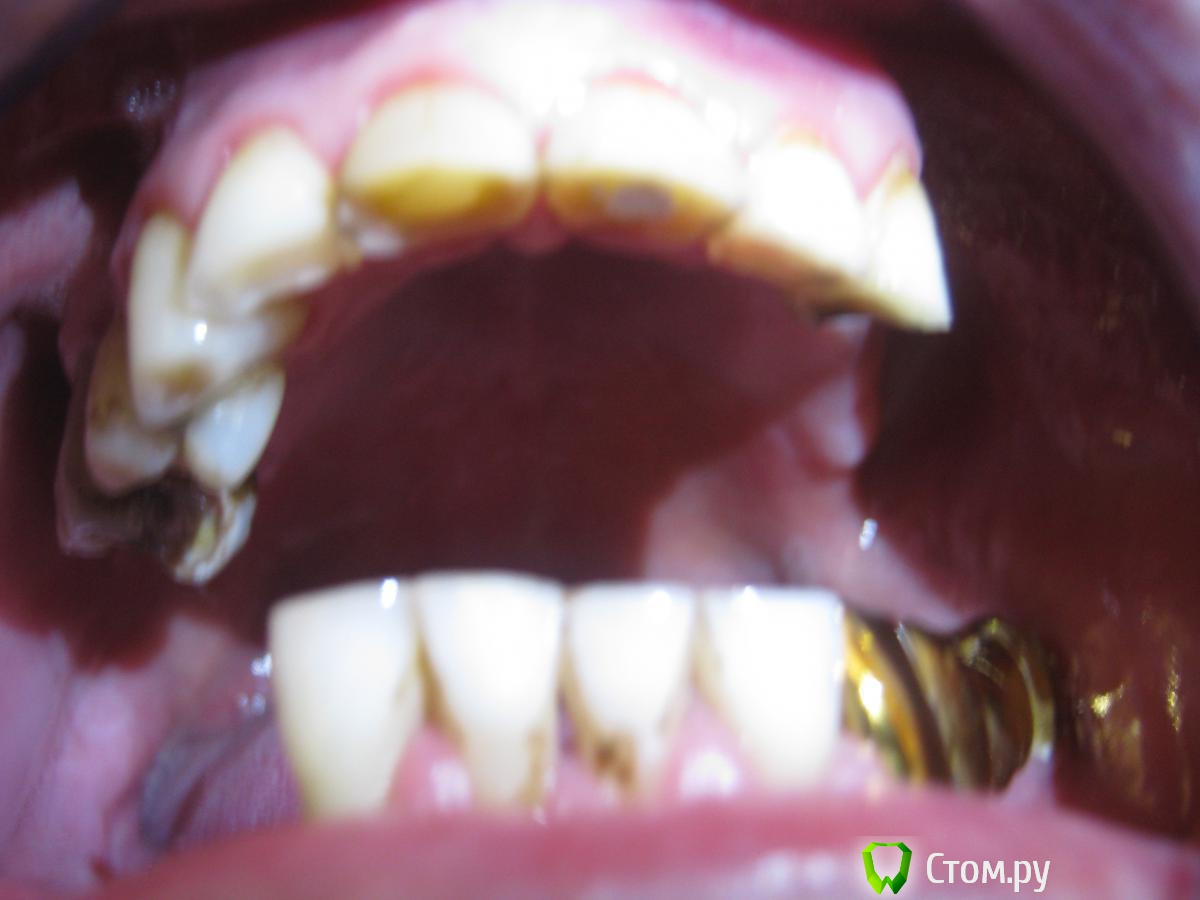

Пациент 49 лет, пришел в клинику с жалобами на боли 21 зуба при накусывании, также хочет протезироваться, зуб 21 поставлен диагноз травматический периодонтит. По словам пациента фронтальные зубы стерлись в течении 3х лет, жевал только фронтом. Коллеги что посоветуете с протезированием? Извиняюсь за качество снимков, Спасибо.